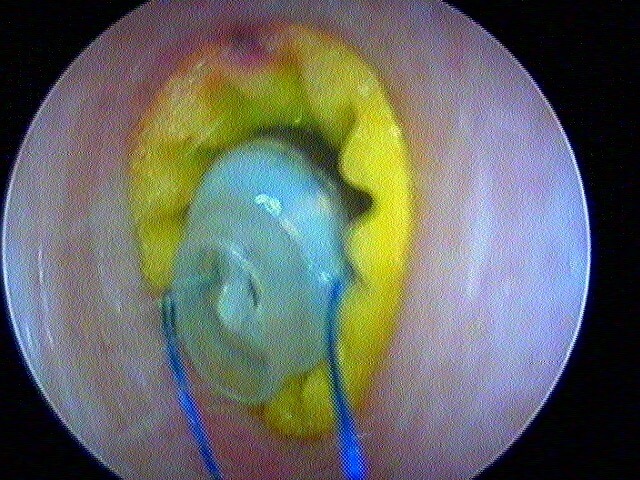

Pour comprendre la paracentèse, ici au laser diode sous A/L au cabinet:

Et la mise en place d'aérateur de type T-tube ici: